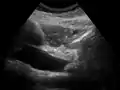

On abdominal ultrasonography, the common bile duct is most readily seen in the porta hepatis (where the CBD lies anterior to the portal vein and hepatic artery). The absence of Doppler signal distinguishes it from the portal vein and hepatic artery.

Borderline of a dilated perihilar bile duct, measuring 8 mm.